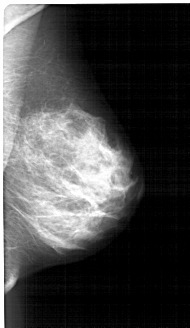

A_1391_1.RIGHT_MLO

RIGHT_MLO LINES 4906 PIXELS_PER_LINE 2836 BITS_PER_PIXEL 12 RESOLUTION 43.5 NON_OVERLAY